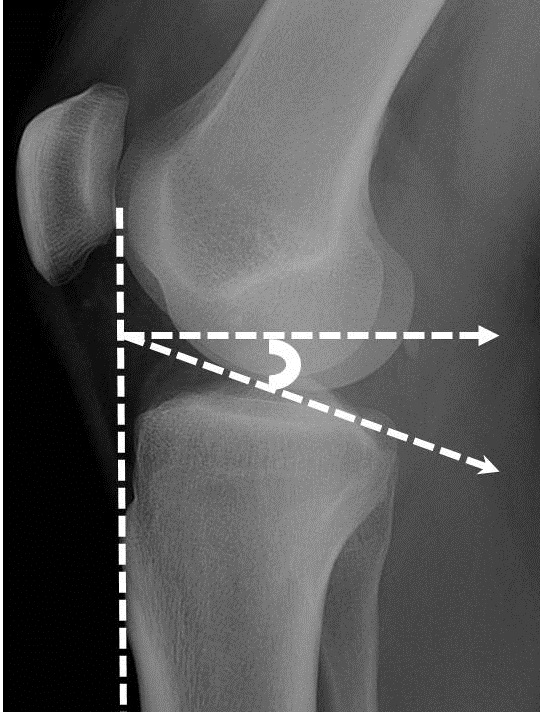

Using a lateral film of the knee, angle is measured by three lines. The first is tangential to the tibial crest, the second is perpendicular to the first line, and the third is tangential to the proximal tibial articular surface. Observe resulting angle from second and third line.

if > 22 degrees then depression ( RID6344 ) due to fracture

how to draw the tibial plateau angle